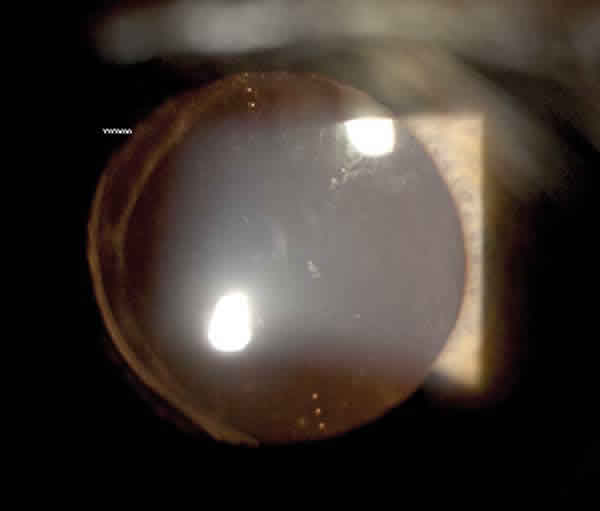

Staar toric IOL® (AA4203TF/TL)

Fue la primera LIO-T aprobada por la FDA, en 1998, y ha sido la más ampliamente estudiada. Es una lente de silicona monobloque con hápticos tipo plato fenestrados (fig. 2). Tras haberse asociado con una rotación excesiva (14), al primer modelo (AA4230T), le siguieron dos nuevos diseños (AA4230TF/TL) con mayor diámetro y fenestraciones más grandes para favorecer la estabilidad frente a la rotación. Dispone de dos potencias cilíndricas, +2 y +3,5D, para corregir aproximadamente 1,4 y 2,3D en plano corneal, y el cálculo de la lente puede hacerse a través de la página web www.staartoric.com.

Fig. 2: Staar toric® (AA4203TL).

Diversos estudios, a pesar de sus diferentes criterios de inclusión, han mostrado una tasa de reducción del astigmatismo refractivo consistente, con agudezas visuales sin corrección (AVSC) superiores a 20/40 entre el 84 y 92% (19,20,21). A pesar de los pobres resultados en cuanto a rotación con el primer modelo (mayor de 20º en un 25%, con un 9,2% de reposicionamientos en el estudio de Sun), la introducción de la lente de mayor diámetro se ha acompañado de una mejoría significativa en su estabilidad, con un 72% dentro de 5º y un 90% menor de 10º (21). Además, esta posición no se modifica tras una capsulotomía posterior tardía con láser Nd:YAG (22).